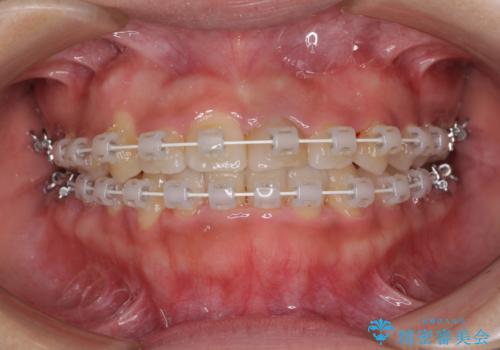

前歯のクロスバイトと変色した歯 ワイヤー矯正とセラミック治療

- 前歯のクロスバイトと神経を取り除いた後に変色してしまった前歯を気にして来院された患者様です。

ワイヤー矯正により矯正治療を行った後に、前歯の補綴治療を行うこととしました。

インビザラインでの矯正治療も十分に対応可能でしたが、自己管理の煩わしさから、ワイヤー矯正を行うこととしました。